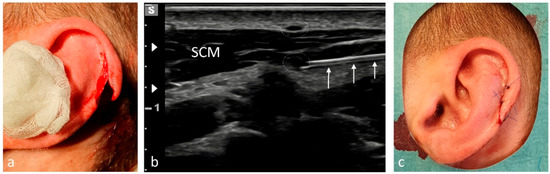

| Clavicle | 48 | Supraclavicular nerves/2–3 |

| AC joint | 11 | Supraclavicular nerves/2–3 |